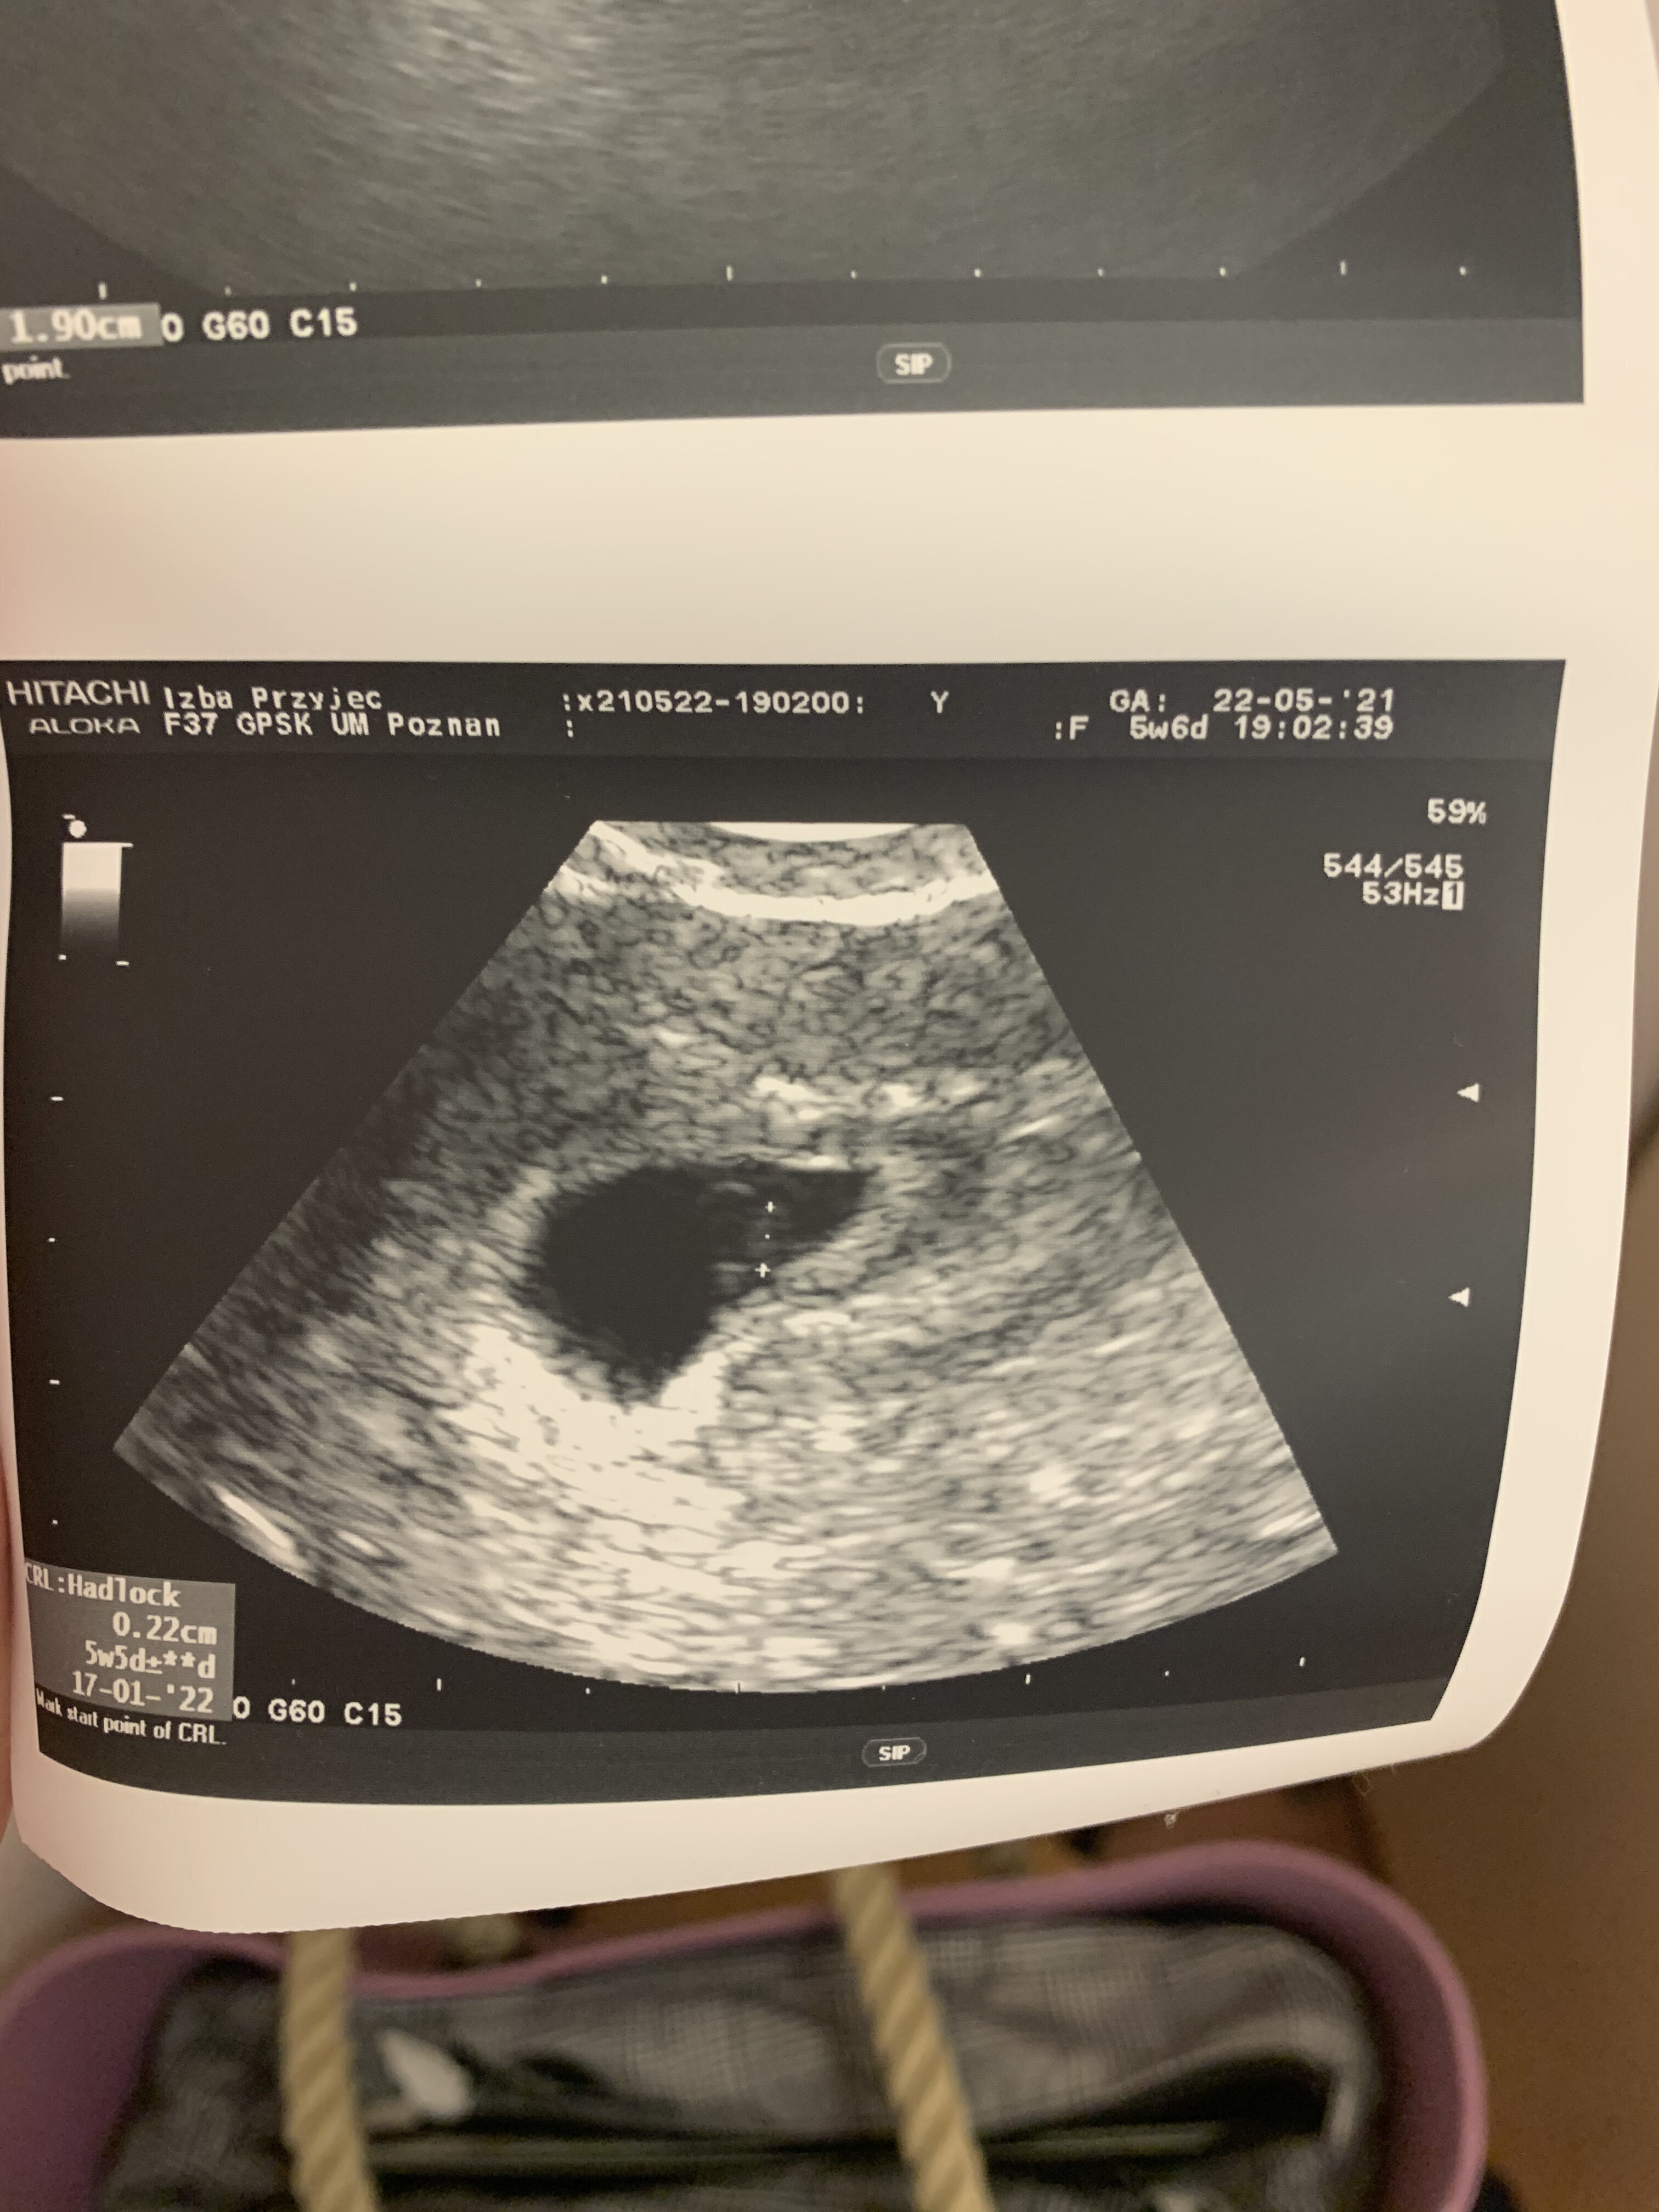

Masakra dziewczyny, ja dziś znikąd dostałam plamienia brązowego (kawa z mlekiem), nie przemeczalam się ani nic z tych rzeczy

Nagle poszłam siku i zobaczyłam plamienie brązowe na wkładce a potem na papierze do toalety. Nie myśląc dużo, pojechalam na izbę przyjęć żeby mnie lekarz zbadał. Oczywiście od razu zaczął pobolewac brzuch jak na okres. Myśląc o najgorszym czekałam najpierw na wymaz, później na wizytę. Co chwile sprawdzałam bieliznę czy nie ma krwi.

Lekarz mnie zbadał, wydzielina lekko brunatna bez aktywnego krwawienia (we wzierniku)

zrobil usg - było widać zarodek, pęcherzyk się zwiększył.

mam brac nospe i luteine 2x100mg

już bylam spokojna ze beta ładna, ze wszystko dobrze przebiega, a tu nagle takie coś... mam nadzieje ze się utrzyma ta ciąża :(